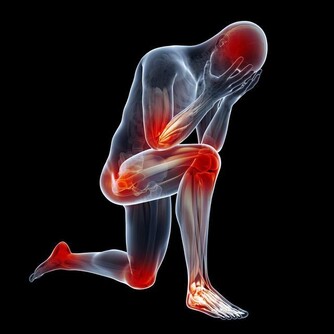

■ 出汗好處3/防治肢體性疾病

其實,「生汗」不僅能排出血液裡的廢物垃圾,稍微增加一點運動量,活動到出汗,還能防治肢體性疾病,如常見的關節炎、關節痠麻沉重、肌肉痛、四肢痙攣等。

有人可能要問,肢體有病還運動,不是往傷口上撒鹽嗎?為什麼運動還能防治關節疾病呢?痛則不通,通則不痛。從中醫角度來講,所有的疼痛疾病,都是由於外邪入侵或身體內部失調,導致氣血淤滯所引發,治療的原則就是疏通經絡,促進氣血流通,而適當的運動,正是疏經活血的最好辦法。

經絡氣血通暢,疼痛就會不治自癒。如果再運動到出汗,侵入經脈的風、寒、濕等病邪垃圾,也會隨著汗液被排除,這就相當於中醫治病的「汗法」,它的作用與吃藥相同。標本兼治,病能不好嗎?